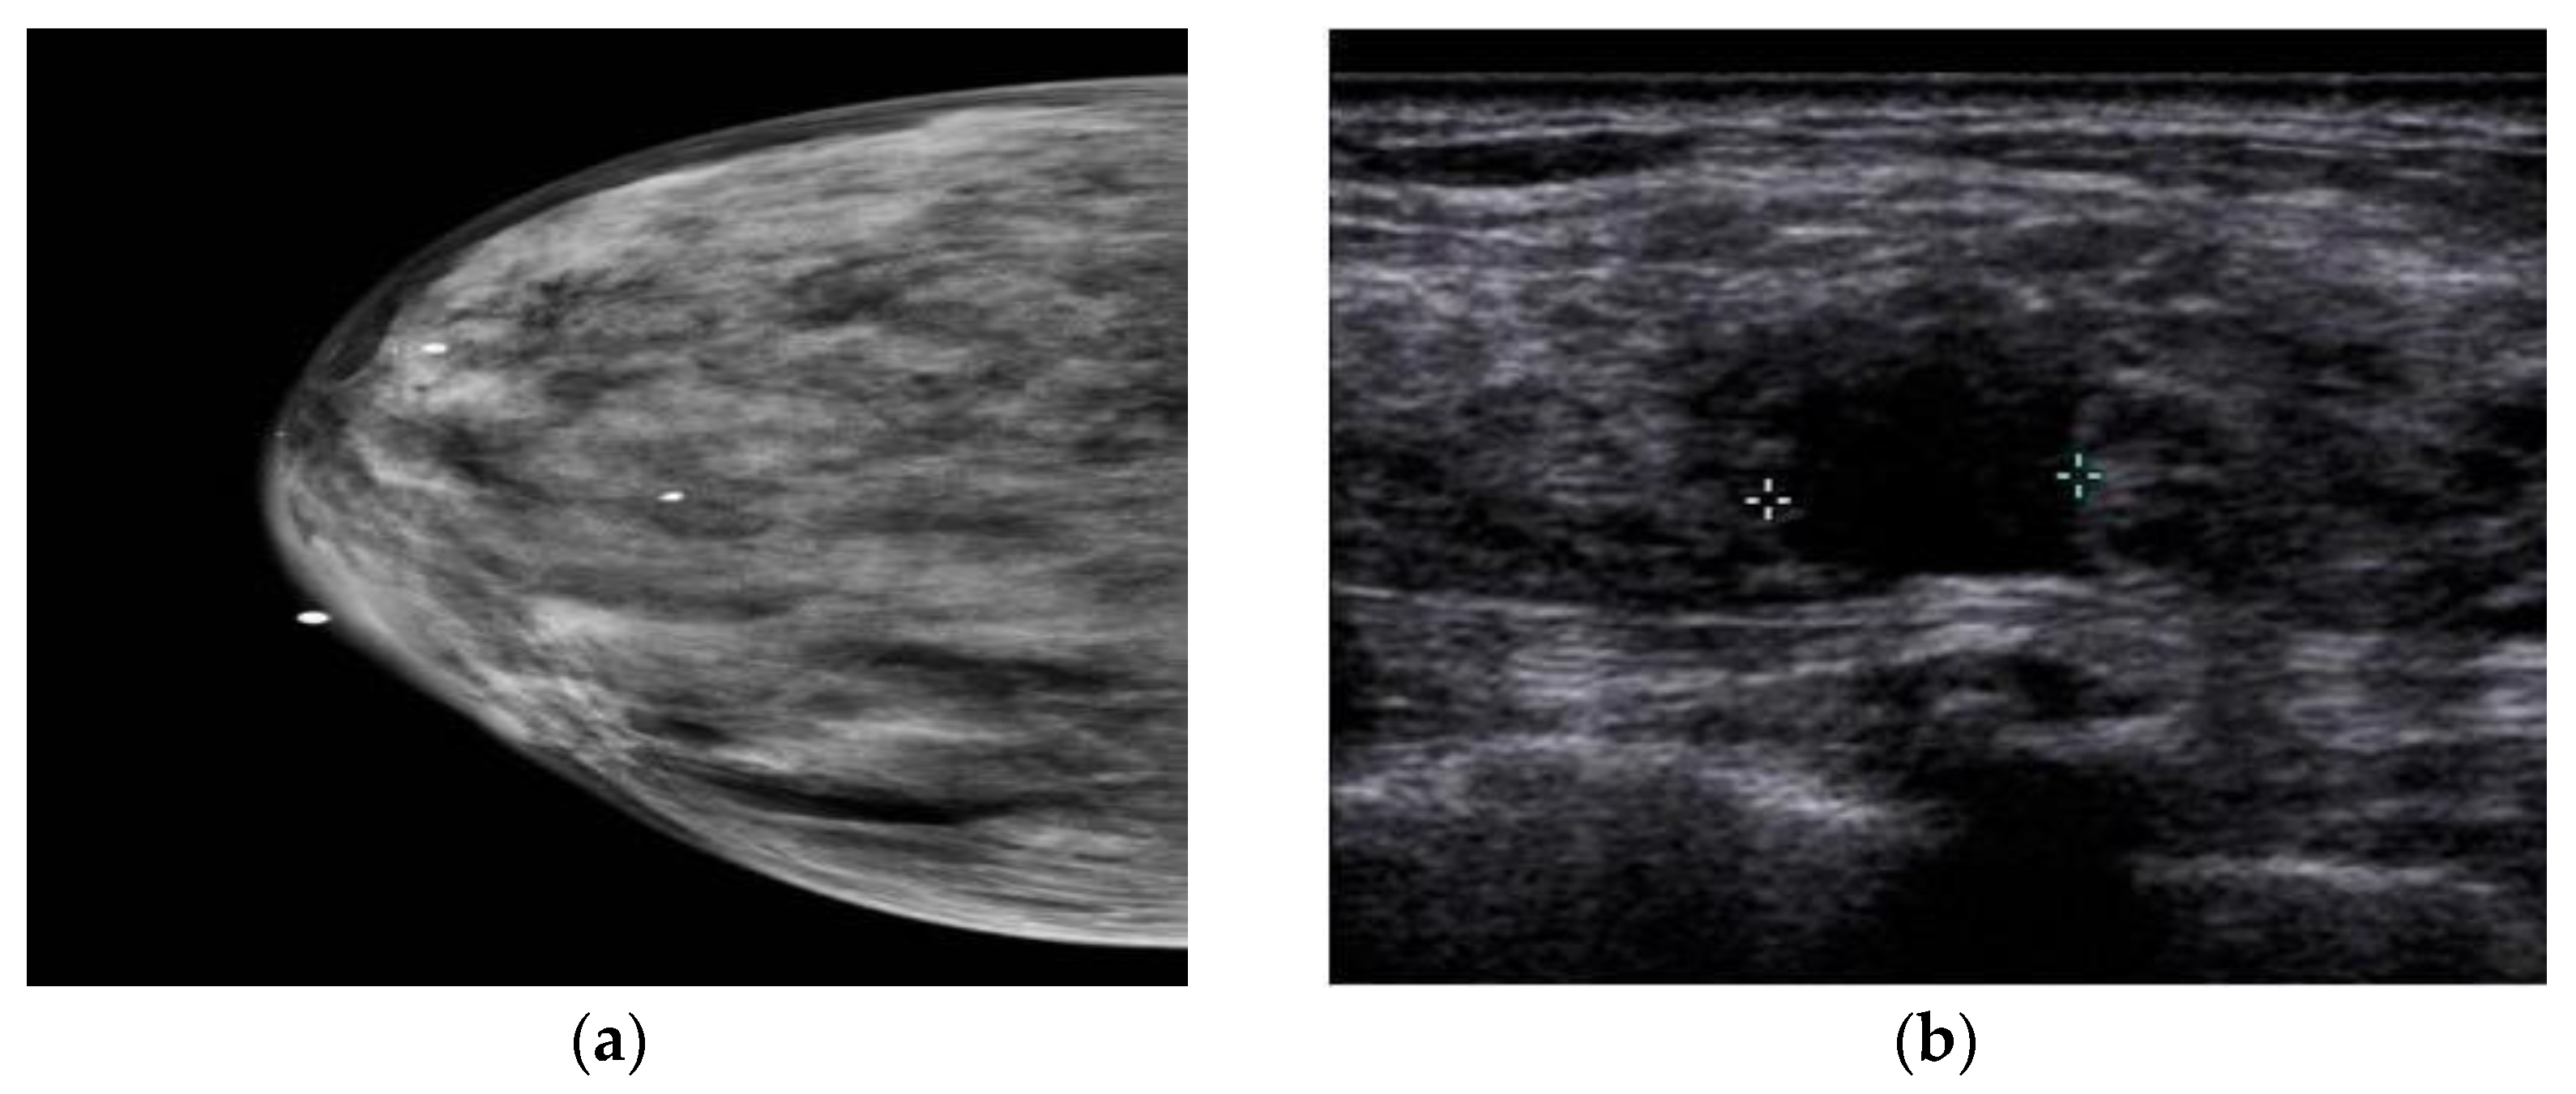

3. Ultrasound Imaging (US)

- Choudhery, S.; Axmacher, J.; Conners, A.L.; Geske, J.; Brandt, K. Masses in the era of screening tomosynthesis: Is diagnostic ultrasound sufficient? Br. J. Radiol. 2019, 92, 20180801. [Google Scholar] [CrossRef]

- Sood, R.; Rositch, A.F.; Shakoor, D.; Ambinder, E.; Pool, K.-L.; Pollack, E.; Mollura, D.J.; Mullen, L.A.; Harvey, S.C. Ultrasound for breast cancer detection globally: A systematic review and meta-analysis. J. Glob. Oncol. 2019, 5, 1–17. [Google Scholar] [CrossRef] [PubMed]

- Iranmakani, S.; Mortezazadeh, T.; Sajadian, F.; Ghaziani, M.F.; Ghafari, A.; Khezerloo, D.; Musa, A.E. A review of various modalities in breast imaging: Technical aspects and clinical outcomes. Egypt. J. Radiol. Nucl. Med. 2020, 51, 57. [Google Scholar] [CrossRef]